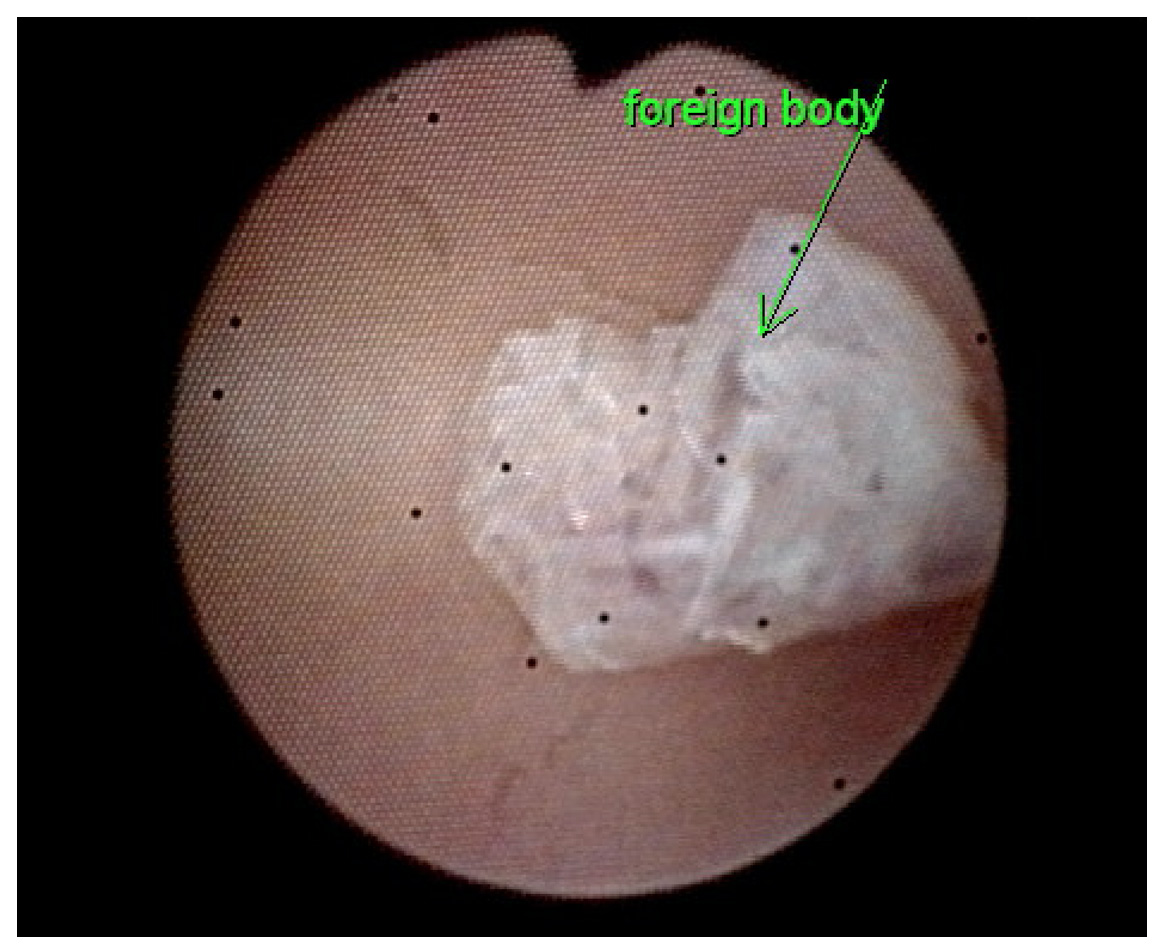

Fig. 2.Diagnostic hysteroscopy. (A) On hysteroscopy, a foreign body presenting as a flattened bundle was seen within the uterine cavity. (B) Gross morphology of the removed specimen.

The second patient, a 35-year-old woman (gravida 3, para 2), presented with abdominal pain in the left lower quadrant for one month. She was previously treated at a regional hospital six weeks ago with laparoscopic surgery and hysteroscopic polypectomy for a tubo-ovarian abscess and an endometrial polyp, respectively. She had evidence of cervical motion tenderness and mildly elevated C-reactive protein levels (7.44 mg/L). Ultrasound revealed an irregular hyperechoic avascular lesion (size: 0.96 cm) located at the isthmus (Fig. 3). Office hysteroscopy identified the presence of a piece of crumpled plastic wrap (Fig. 4). Histologically, the proliferative-phase endometrium shows scattered plasma cells and neutrophils in the stroma and infiltration of neutrophils into the surface epithelium. Acute and chronic endometritis caused by a previously positioned membranous AAB was confirmed. Metronidazole 500 mg every 12 hours for 3 days was prescribed and she had no specific urogenital complaints for the next 12 months.

Fig. 4.Office hysteroscopy identified a piece of crumpled plastic wrap at the isthmus.